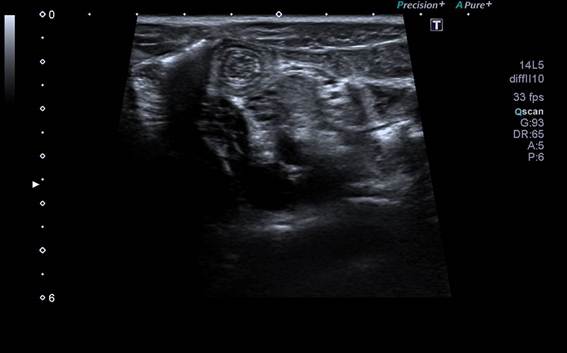

En la ecografía se hallan ganglios reactivos en fosa ilíaca derecha e invaginación ileo-ileal con imagen en diana, resuelta de forma espontánea mediante la compresión de la sonda ecográfica, confirmando el diagnóstico de adenitis mesentérica con invaginación intestinal secundaria.